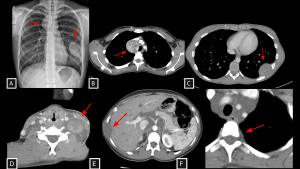

Fig 8: Cases 8 and 9 – Malignant neural-lineage neoplasm presenting as a visceral mediastinal mass and Neurofibromas.

A 21-year-old patient with a history of neurofibromatosis type 1 undergoing evaluation for cough and constitutional symptoms. Chest radiograph (A) showed mediastinal widening and a left pulmonary mass. Corresponding to the radiographic findings, contrast-enhanced chest CT (B and C) demonstrated two heterogeneous expansile lesions located in the visceral mediastinum and left thoracic wall, containing hypoattenuating foci (likely cystic components). Biopsy of the right paratracheal lesion revealed a malignant peripheral nerve sheath tumor.

Case 9 (D–F) demonstrates disseminated plexiform neurofibromas: a neck mass splaying carotid space vessels without stenosis (D), multiple fusiform hypoattenuating intercostal lesions (E), and extensive retroperitoneal soft tissue encasing the aorta and celiac trunk (F).

MPNST (Malignant Peripheral Nerve Sheath Tumor) SYSTEMATIC APPROACH: 1. Age: Adults (increased risk in NF1). | 2. Morphology: Large, ill-defined mass with necrosis/hemorrhage. | 3. Enhancement: Heterogeneous/Peripheral. | 4. Relevant Anatomical Relationships: Invasive; rapid growth with destruction of adjacent planes.

Neurofibroma SYSTEMATIC APPROACH: 1. Age: Pediatric/Young Adults (NF1 context). | 2. Morphology: Diffuse, infiltrative ("Bag of worms"). | 3. Enhancement: Variable. | 4. Relevant Anatomical Relationships: Multicompartmental; involves nerve plexuses/branches.